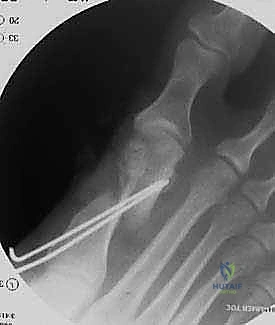

هذه هي اللحظة الحاسمة في العملية. يقوم الدكتور هطيف بإجراء القص العظمي على شكل حرف (V) ممتد. دقة زاوية القص هنا تحدد نجاح العملية بالكامل.

الخطوة الثالثة: القص العظمي الممتد (The Extended Osteotomy)

باستخدام منشار جراحي متذبذب دقيق جداً، يقوم الدكتور هطيف بعمل قطع عظمي على شكل حرف (V). يتميز هذا القطع بأن ذراعه السفلي يمتد طويلاً على طول محور العظم المشطي. يتم توجيه القطع بزوايا ثلاثية الأبعاد محسوبة مسبقاً لتجنب قصر إصبع القدم أو ارتفاعه عن الأرض بعد الجراحة.

إدخال أسلاك التوجيه (K-wires) لتثبيت العظم مؤقتاً والتأكد من الوضعية الصحيحة باستخدام جهاز الأشعة السينية داخل غرفة العمليات (C-arm) قبل وضع المسامير النهائية.